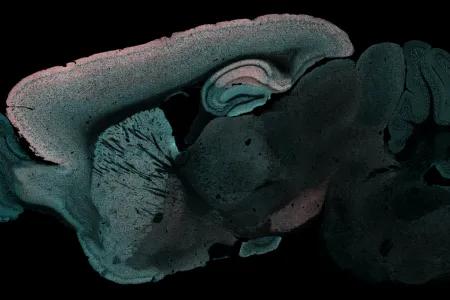

Mouse brain showing red areas where protein exchange occurs most slowly.

They also discovered that the protein exchange occurs slowest in those areas of the brain responsible for long-term memory.